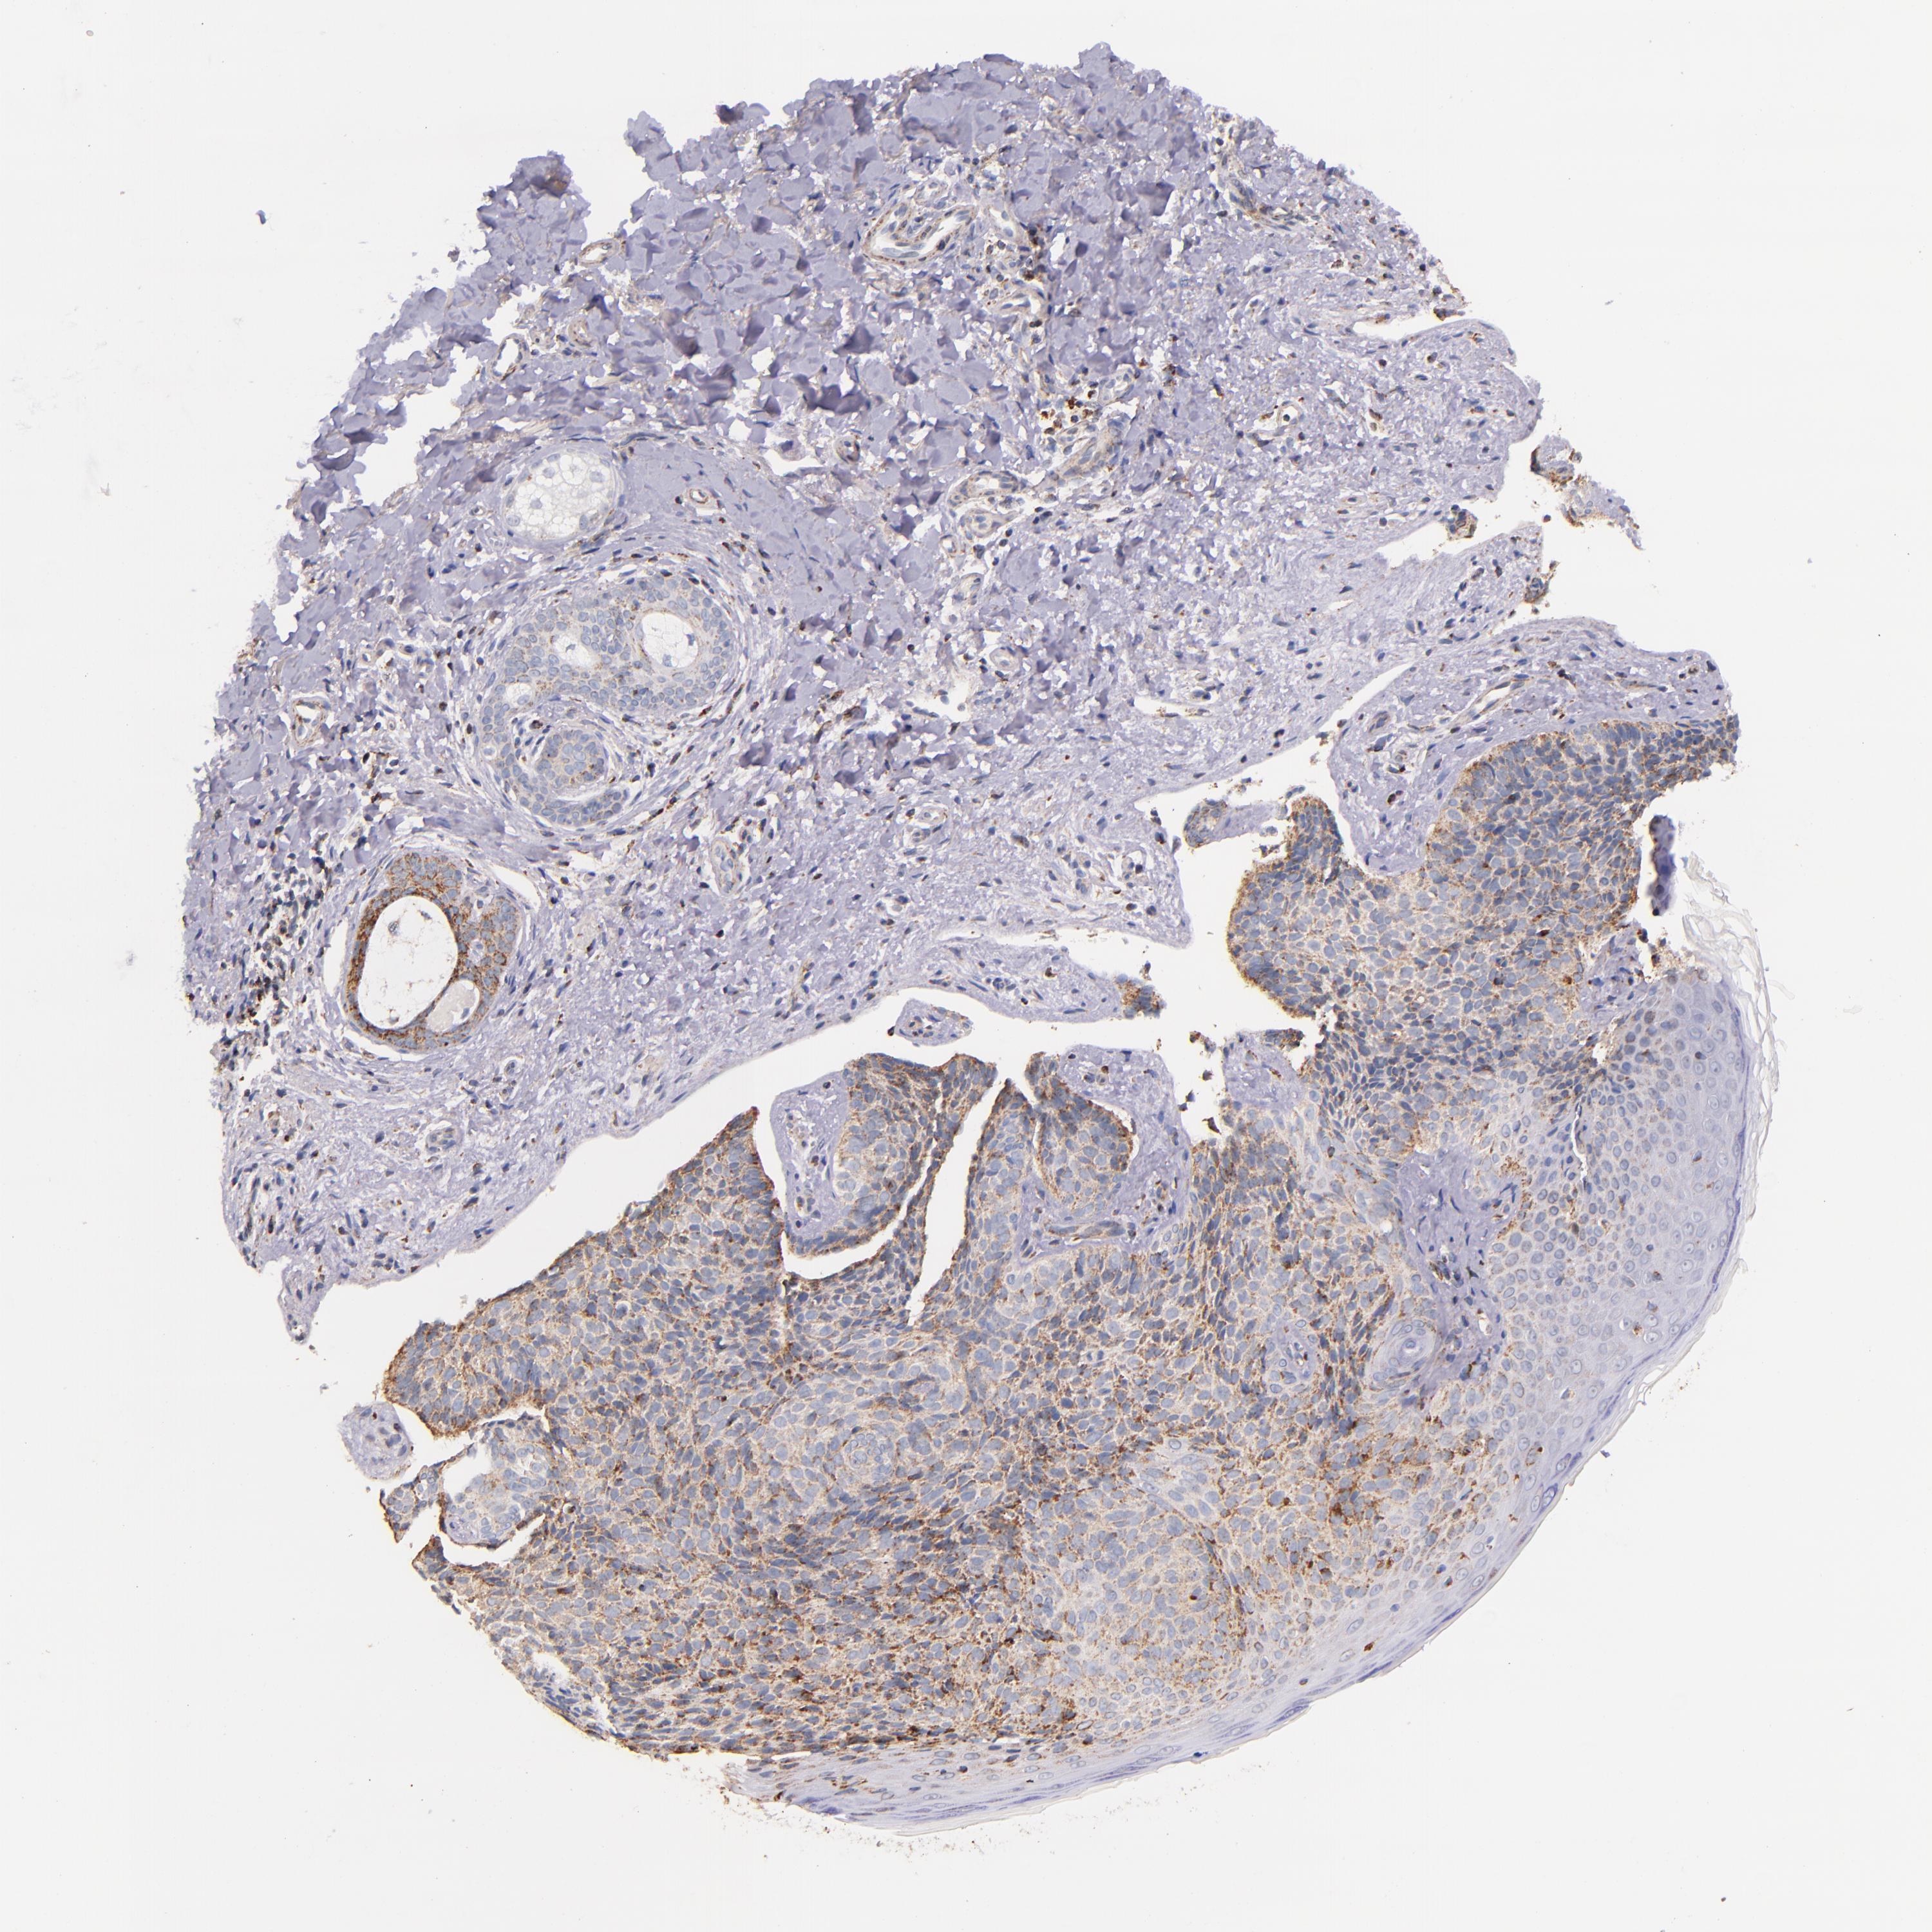

Basal cell and squamous cell cancer

SKIN CANCER - Protein expressioni

A mouse-over function shows sample information and annotation data. Click on an image to view it in a full screen mode. Samples can be filtered based on level of antibody staining by selecting one or several of the following categories: high, medium, low and not detected. The assay and annotation is described here.

Antibody stainingi

Antibody staining in the annotated cell types in the current human tissue is reported as not detected, low, medium, or high, based on conventional immunohistochemistry profiling in selected tissues. This score is based on the combination of the staining intensity and fraction of stained cells.

Each image is clickable and will lead to virtual microscopy that enables deeper exploration of all samples and also displays staining intensity scores, fraction scores and subcellular localization as well as patient and tissue information for each sample.

Antibody HPA000425

Antibody HPA002017

Staining

High

Medium

Low

Not detected

Intensity

Strong

Moderate

Weak

Negative

Quantity

>75%

75%-25%

<25%

None

Location

Nuclear

Cytoplasmic/membranous

Cytoplasmic/membranous,nuclear

Squamous cell carcinoma, NOS

Basal cell carcinoma